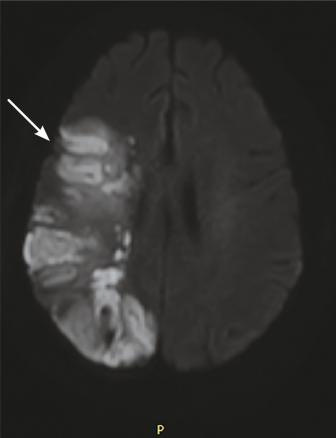

Cette femme de 45 ans était admise aux urgences à la suite d’une hémiplégie gauche. Une imagerie par résonance magnétique (IRM) cérébrale montrait un accident vasculaire cérébral ischémique aigu du territoire de l’artère cérébrale moyenne droite (fig. 1 ) avec occlusion de l’artère carotide droite. Par ailleurs, il y avait un comblant otomastoïdien droit (fig. 2 ) avec collection abcédée parapharyngée homolatérale (fig. 2 ) et thrombose de la veine jugulaire interne droite étendue au sinus sigmoïdien et latéral (fig. 3 ). Après 21 jours d’antibiothérapie intraveineuse combinée à l’anticoagulation, l’IRM de contrôle montrait une recanalisation de la carotide interne et de la veine jugulaire interne.

Le syndrome de Lemierre est une entité rare et potentiellement grave, définie par la survenue d’une thrombophlébite cérébrale touchant la veine jugulaire interne ou ses bran-ches. Il est dû, le plus souvent, à une infection par Fusobacterium necrophorum.1 Le site initial est généralement oropharyngé. En l’absence d’une antibiothérapie précoce et adaptée, ce syndrome peut rapidement évoluer vers une septicémie et à la dissémination par voie hématogène à d’autres sites métastatiques.2 L’occlusion de la carotide interne et la survenue d’un infarctus cérébral sont des complications extrêmement rares et exceptionnelles de ce syndrome.